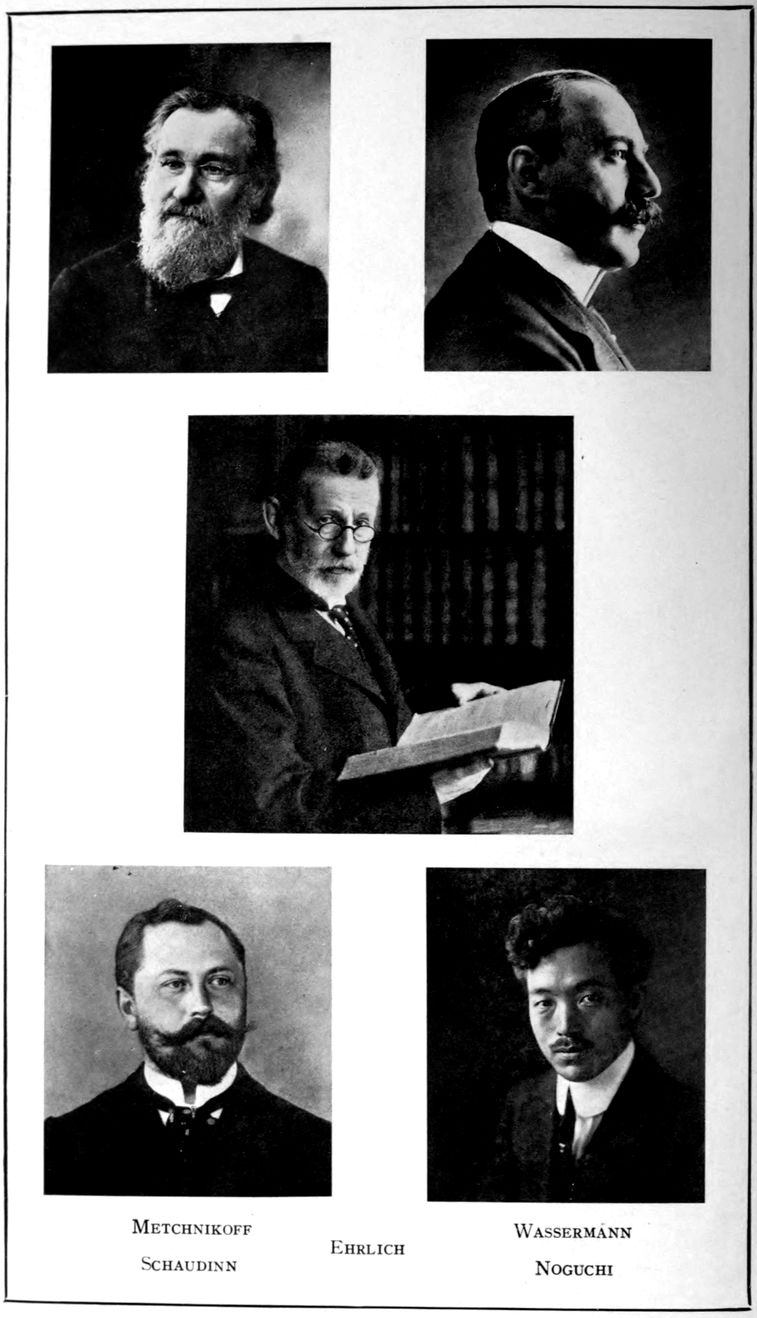

It is a privilege to be allowed to write a word of introduction to a textbook which so richly fulfils its function as does this volume on the manifold disorders classified under Neurosyphilis, a subject of which the importance for the welfare of society is found to loom the larger the more deeply its mysteries are probed.

The case histories with which its pages are so amply stocked are carefully analyzed in accordance with a broadly chosen plan, and the generalizations that precede and follow them are obviously based on a wide and varied personal experience such as alone could render a familiarity with the literature of the subjects treated adequate to its best usefulness. Both writers were indeed well adapted for this task. Dr. Southard, as everyone is aware, has long been a highly conscientious, ardent and productive worker in the department of pathological anatomy, and of late years a careful student of clinical diagnosis and methods, both at the Danvers State Hospital and still more, at the Psychopathic Hospital which he worked so hard to found; while Dr. Solomon’s researches, in the special field of neurosyphilis, have been of the highest order.